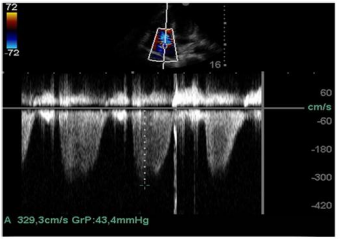

Ainda com o uso da ecocardiografia beira-leito, realizou-se a mensuração da pressão sistólica do ventrículo direito por meio da análise do refluxo tricuspídeo demonstrando o valor de 43,4 mmHg, como apresentado na imagem.

Com base nessas informações e nas imagens, a estimativa da pressão sistólica da artéria pulmonar é de